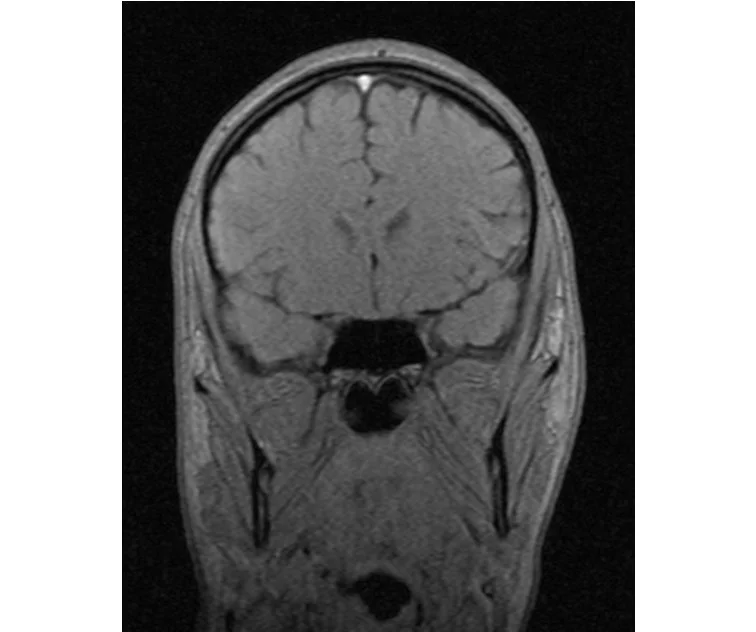

делал в обласной на siemense.В заключении выданом мне через 15мин.после мрт (легкая дегидрация)

Меня смутил факт выдачи заключения через 10мин(наверно они у них зарание напечатаные)я не медик.достаточно мимолётного взгляда на снимки?А вы видете на них гидроцефалию? Я лиш спросил куда идти с результатами томографии?и не хотел никого роздражать.

Я попросил взглянуть на снимки и сказать видна.ли на них гидроцефалия?или куда обратится за консультацией по этому вопросу?В мрт снимках наверно розбирается любой нервопатолог(я так предположил)

Я уже говорил, что независимо от того, есть на МРТ гидроцефалия или нет, лечиться тебе нужно только в том случае, если есть какие-либо проявления болезни, иначе на все эти анализы можешь забить... Но давай все-таки разберемся с томограммой.

Итак, с самого начала томограмма обозначала срез какого-либо органа на определенной глубине, позволяла заглянуть вовнутрь. При компьютерной томографии аппарат делает десятки срезов головного мозга в разных направлениях и из этого множества срезов он моделирует полноценное объемное изображение мозга в натуральную величину. Обрати внимание, компьютер работает не с этими миниатюрными изображениями, а с трехмерной моделью в масштабе 1:1. Эту модель вдоль и поперек анализирует суперсовременный компьютер, выполняющий миллионы операций в секунду. Только ***** может пытаться перепроверить компьютер, ведь человеку не хватит всей жизни чтобы проанализировать то, что компьютер с тобой сделал за 10 минут. Я хочу, чтобы ты это понял!

Ты разместл здесь несколько миниатюр и хочешь, чтобы врач по ним создал полноценное объемное изображение в натуральную величину, а потом осмотрел его со всех сторон и дал заключение? Но ведь это невозможно. Это просто насмешка над врачом, это издевательство над здравым смыслом. Принеси Букеру уменьшенный в 50 раз снимок зуба и спроси у него, в каком состоянии там корневые каналы. Или давай я дам тебе скрин со спутниковой карты города и попрошу тебя описать, какого цвета и какой модели запечатленная со спутника машина, какой у нее гос.номер, сколько в ней пассажиров, сколько из них мужчин и сколько женщин...